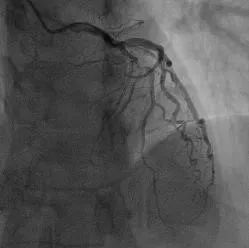

11:56,行冠脉造影检查,结果显示心脏冠脉左前降支最重处99%狭窄。和想象中的一样,患者血栓已经非常严重。

术前血管被堵住